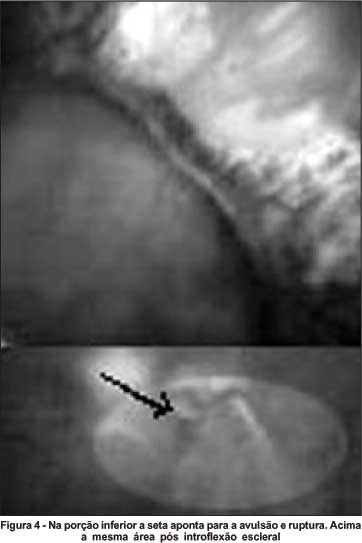

A análise identificou 13 olhos que obedeciam aos critérios propostos. Destes, 8 foram submetidos a fotocoagulação com laser de argônio verde e 5, a introflexão escleral com explante (esponja) localizado (Figuras 1, 2, 3, 4). Os principais aspectos examinados estão contidos na tabela 1. Do total, 6 casos eram do sexo masculino e 7, feminino. Idade oscilou entre 30 e 70 anos, média 53,6 anos.